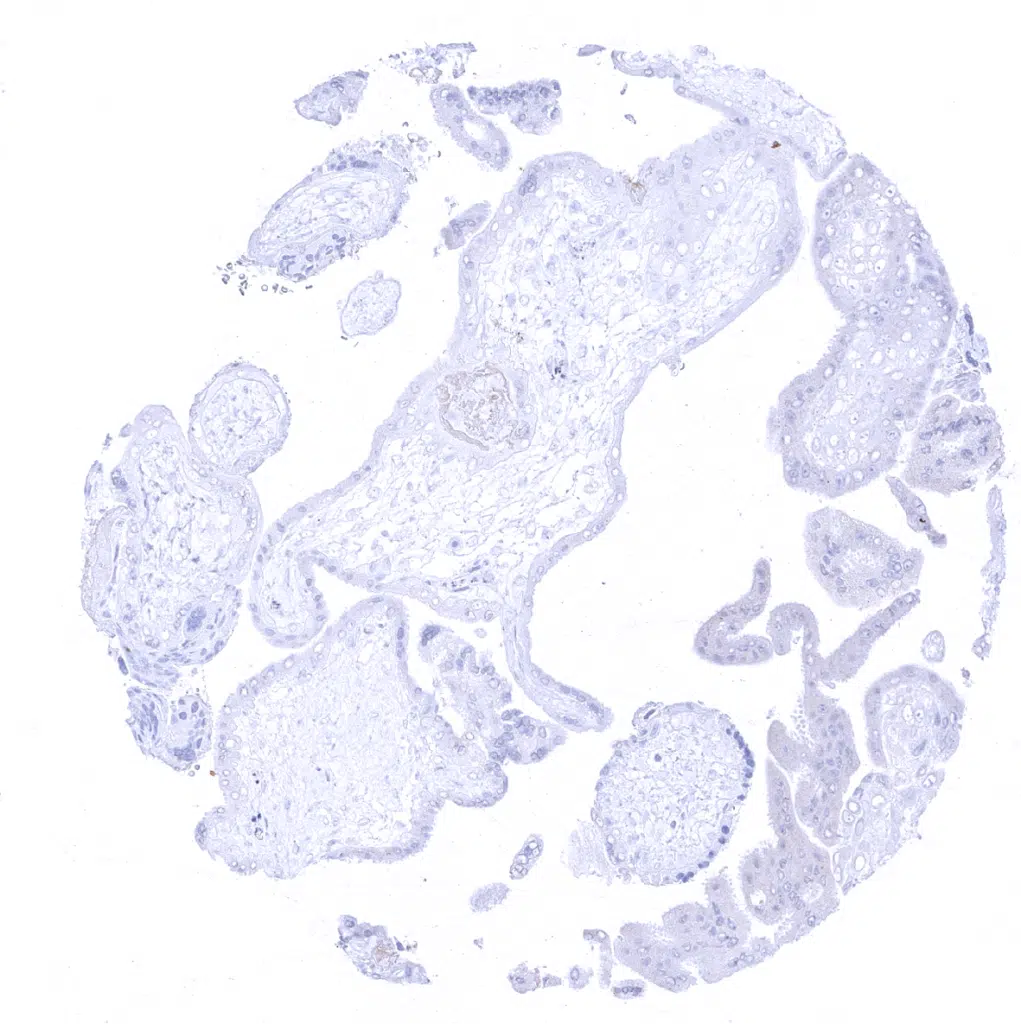

Placenta, early

Placenta, mature

Placenta (amnion and chorion)